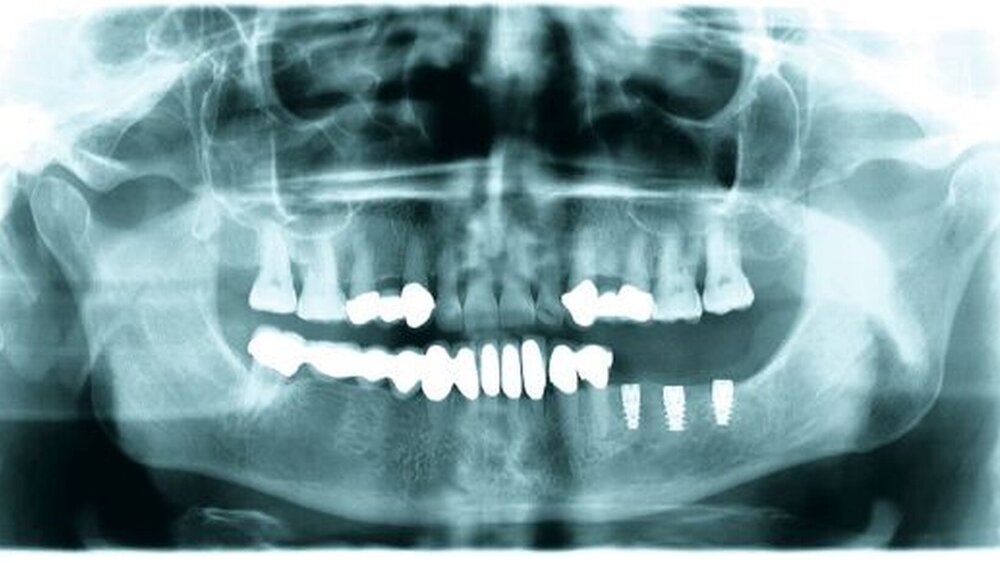

Daraus ergibt sich folgende Therapieplanung mit konzeptionell verkürzter Zahnreihe, die sich in der Praxis seit Jahren bestens bewährt (Abbildungen 4, 5, 6) [Luthardt et al., 2000; Jivraj und Chee, 2006]:

Grunduntersuchung Implantologie: Nach erfolgter PAR-Therapie und/oder Zahnentfernung erfolgen Definitivplanung mit präoperativem OPG, Beurteilung der Kieferkammbreite (Schieblehre) und Erstellung des Kostenvoranschlags IMP, Abformung für Messschablone, DVT (Kosten!) nur bei kritischem Knochenangebot oder Anatomie [Walter et al., 2009].